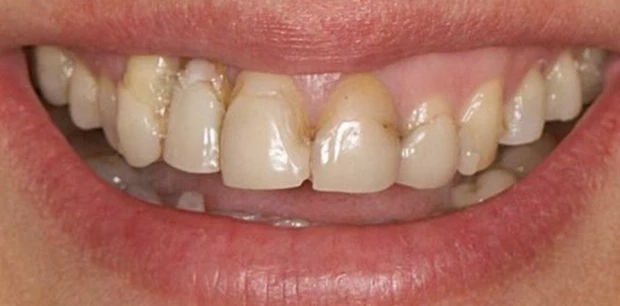

Профгигиена

Профессиональная гигиена зубов

Пациент Ф., 27 лет обратился с жалобами на периодическую кровоточивость десен при чистке зубов и на скученность зубов. Проведена профессиональная гигиена полости рта, пациент направлен на ортодонтическое лечение.